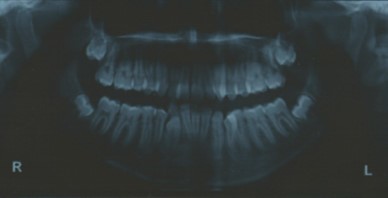

Radiographic assessment. The panoramic radiograph confirmed the presence of all permanent teeth with the presence of 18, 28, 38 and 48 tooth germs with normal alveolar bone levels. (Figure 2).

Figure 2.Pre-treatment panoramic radiograph

Pre-treatment panoramic radiograph